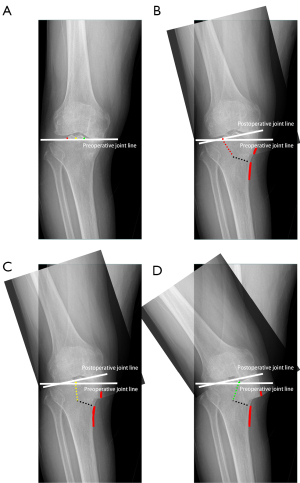

Preoperative deformity and hinge position are associated with the magnitude of the gap opening during the corrective osteotomy. A systematic review revealed an increased risk of lateral hinge fracture when the wedge is opened by >11 mm during OWHTO (10). The larger the magnitude of the opening gap is, the more medially aligned the medial portion of the proximal fragment and the more laterally aligned the medial portion of the distal fragment (11). A similar trend has been observed during TCVO, which is considered a special type of OWHTO (Figure 1). In such circumstances, a larger degree of mismatch between the patient-specific bony surface and the factory-made locking plate can impose a higher stress on the construct and weaken the structural stiffness of the implant, leading to an increased risk of technical complications, such as hinge fracture, screw pullout, and plate breakage (12-15). In addition, the significant prominence of the implant beneath the medial subcutaneous border and the small contact area between the plate and the bone at the distal end can cause postoperative pain (11,15). Thus, the hinge position that leads to the smallest gap opening angle should be favored by surgeons during TCVO.

The opening angle refers to the angle formed between 2 osteotomy lines after opening the osteotomy gap. The opening angle was measured by a ruler and confirmed by plotting the opening wedge on the intra-operative radiograph during the gap opening (Figure 2). The preoperative evaluations and all the operations were performed by 2 surgeons. Surgical indications and details of the TCVO procedures were similar to those described previously (5,6). Radiographic measurements were recorded twice by 2 independent observers at an interval of 6 weeks. The examiners were blinded to each other’s results. The intra- and interrater reliability of the measurements were assessed by examining the intraclass correlation coefficients.

- For the preliminary analysis of the simulated realignment process at the coronal plane, the preoperative joint line was set to pass through the selected 3 hinge points, as the distance of these hinge points to the preoperative joint line was negligible compared to the distance between these 3 hinge points. The simulated gap opening procedure was performed by rotating the medial tibial plateau and distal femur around the selected hinge point until the lowest point of the medial tibial plateau became tangential to the postoperative joint line (Figure 4). The opening angle α subtended lines from the hinge points to the medial margin of the tibia on the preoperative joint lines and hinge points to this medial margin of the tibia after simulation.

A 2-dimensional (2D) schematic model of genu varum is shown in Figure 3, and the simulated realignment process at the coronal plane is shown in Figure 4. The opening angle with the hinge point at the lateral beak of the intercondylar eminence (αa) was the smallest, while the gap opening angle with the hinge point at the medial beak of the intercondylar eminence (αc) was the largest.